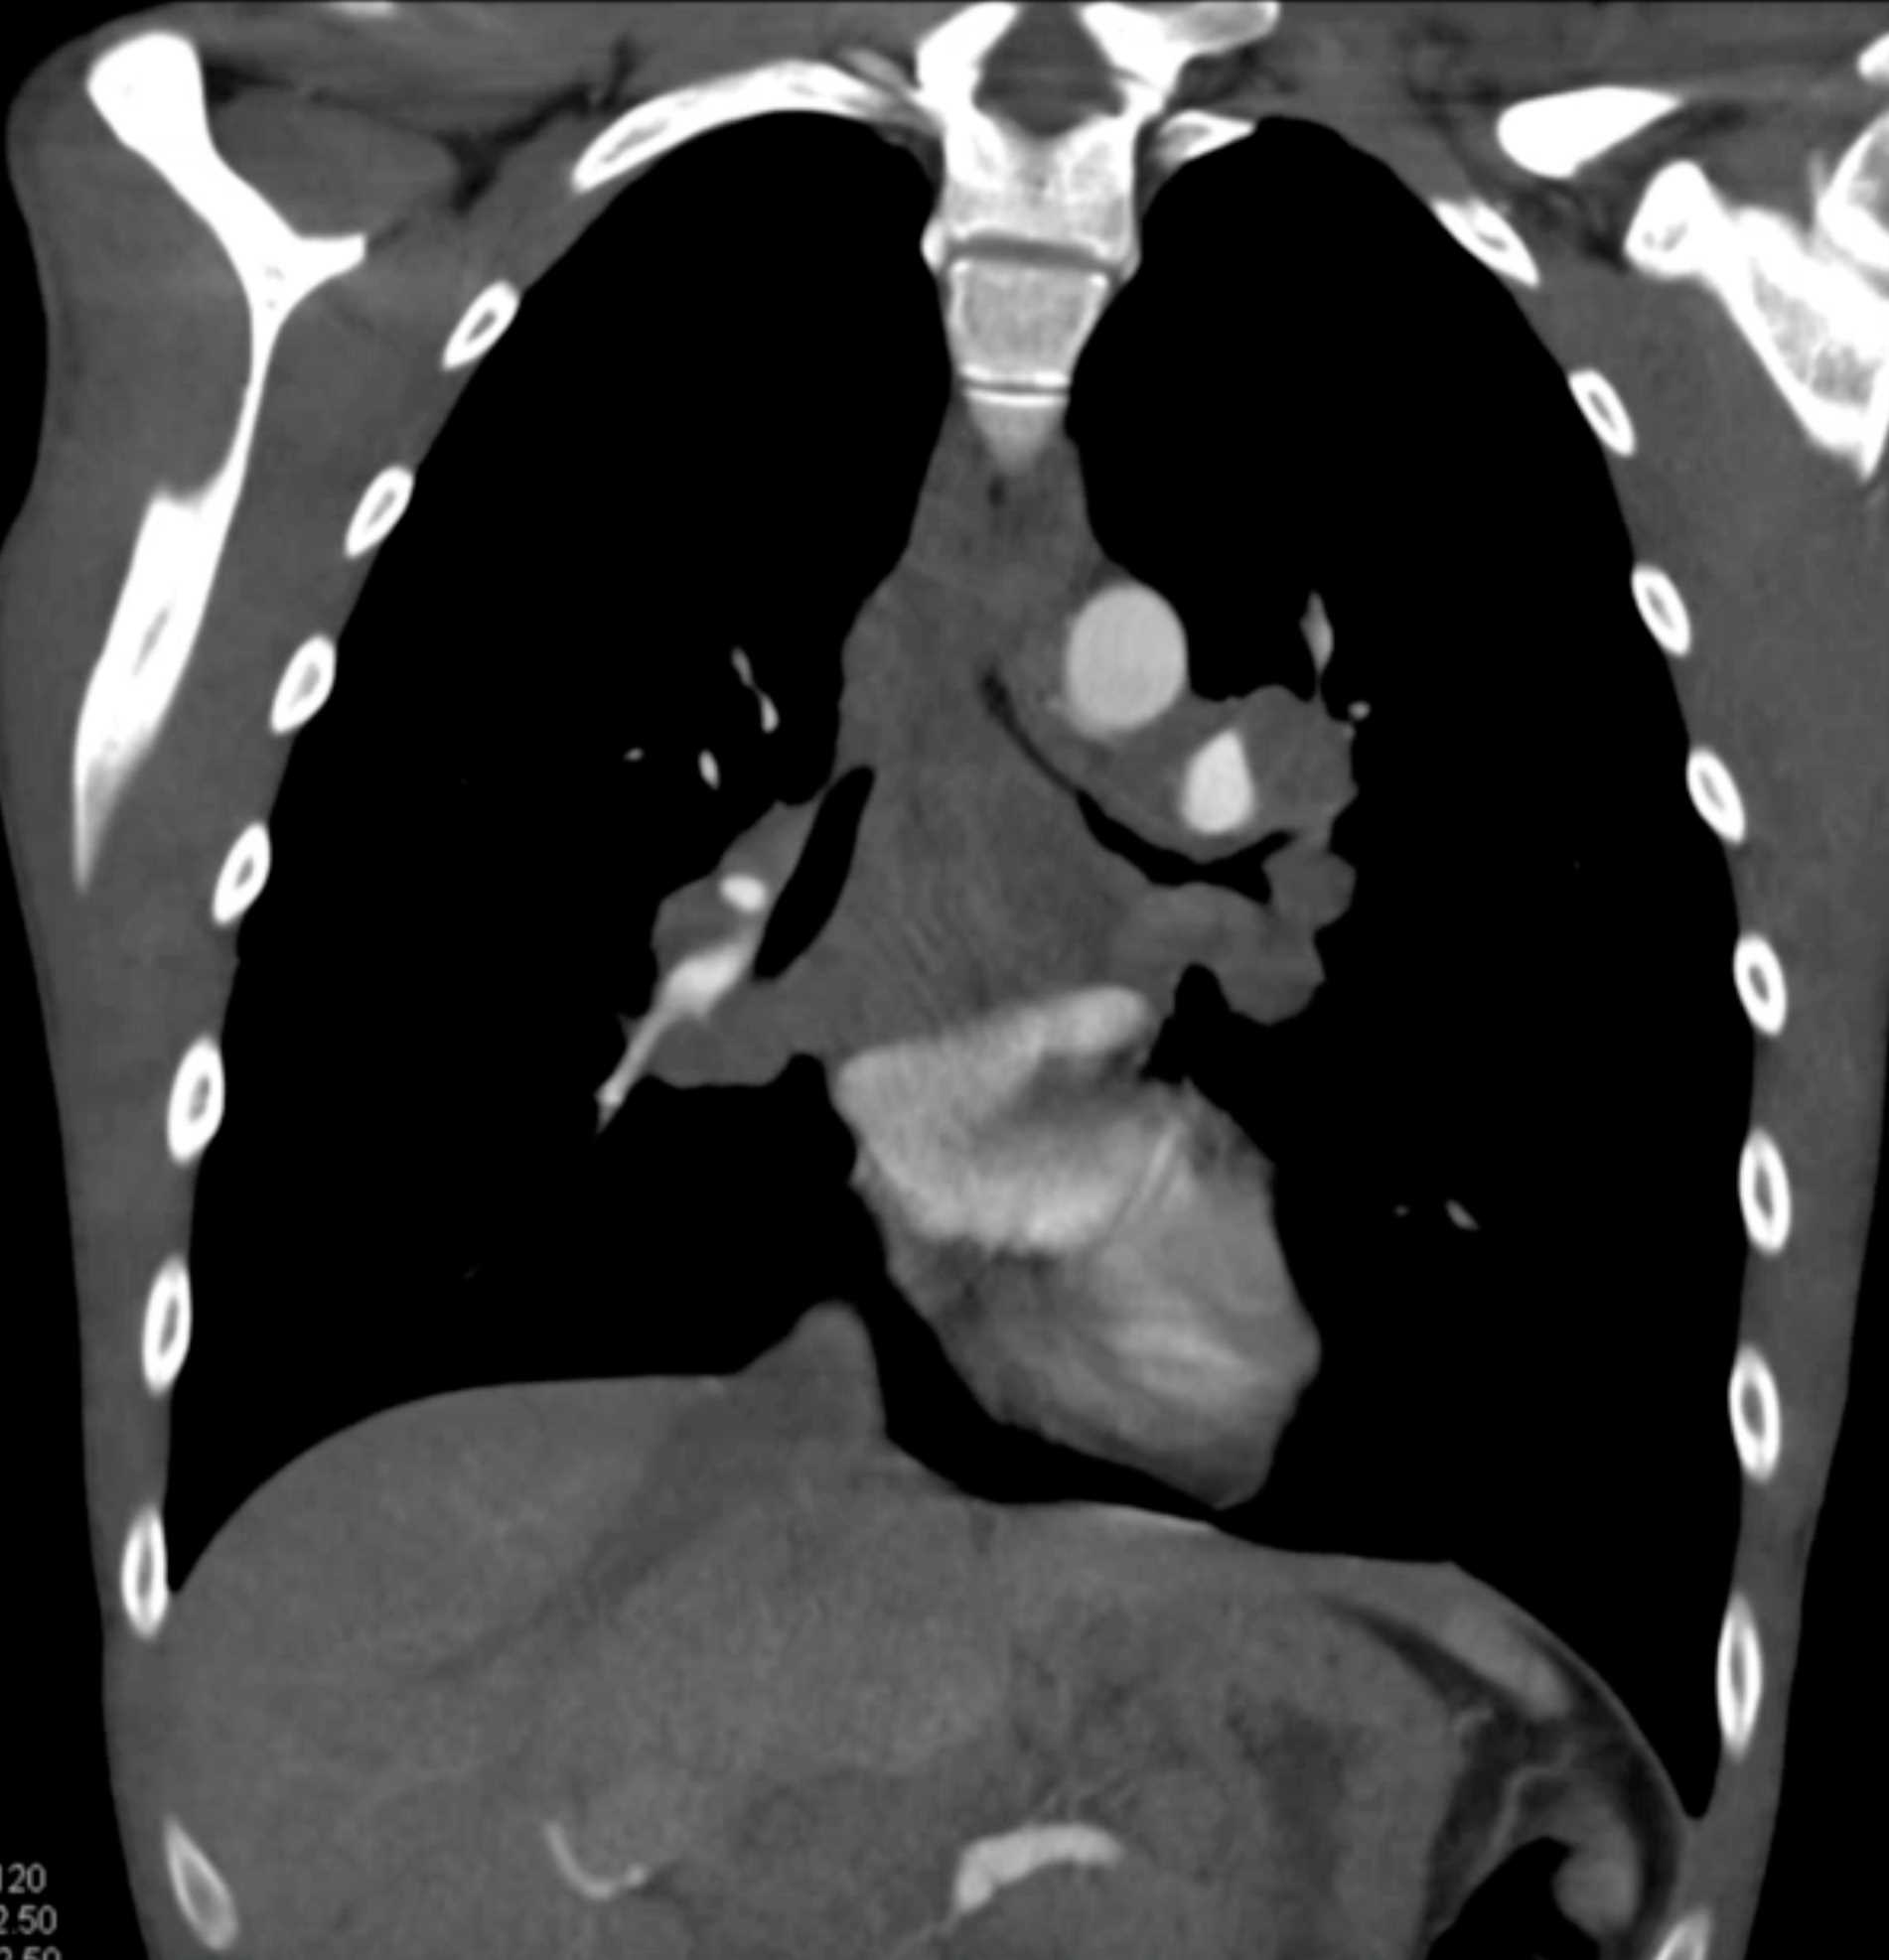

Large Cell Lymphoma